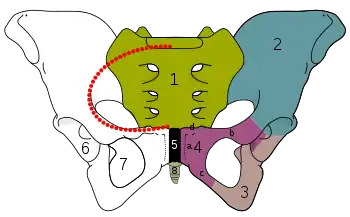

The pelvic inlet (shown in red) | |

The pelvic inlet or superior aperture of the pelvis is a planar surface which defines the boundary between the pelvic cavity and the abdominal cavity (or, according to some authors, between two parts of the pelvic cavity, called lesser pelvis and greater pelvis). It is a major target of measurements of pelvimetry.

Its position and orientation relative to the skeleton of the pelvis is anatomically defined by its edge, the pelvic brim. The pelvic brim is an approximately apple-shaped line passing through the prominence of the sacrum, the arcuate and pectineal lines, and the upper margin of the pubic symphysis.

Boundaries

The edge of the pelvic inlet (pelvic brim) is formed as follows:

| Anteriorly by the pubic crest (or pubic symphysis) | ||

| Laterally by the iliopectineal line | (same as other side) | |

| Posteriorly by the anterior margin of the base of the sacrum (or the ala of sacrum) and sacrovertebral angle (or sacral promontory) |